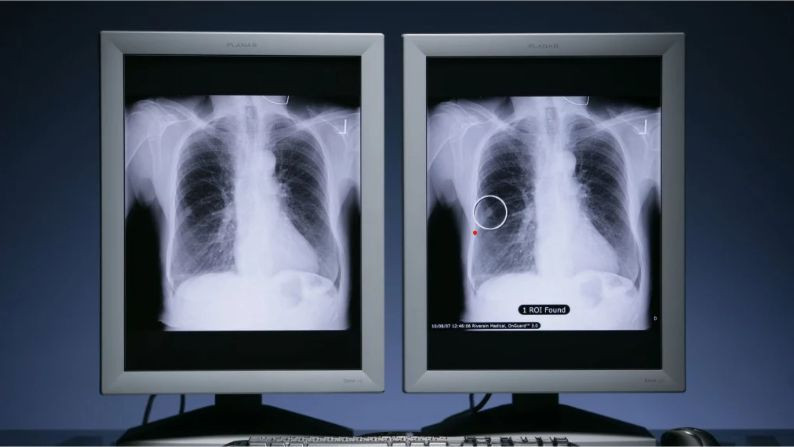

Ung thư phổi là loại bệnh phổ biến nhất trên toàn thế giới, ước tính có 2,5 triệu ca mới trên toàn cầu vào năm ngoái. Ảnh: PR NEWSWIRE.